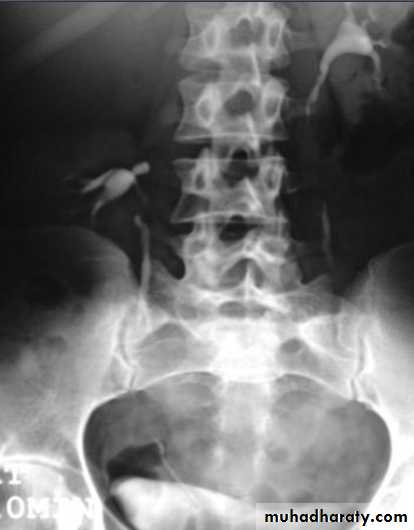

KUB.

Non visualization of the Rt. Kidney either due to early obst. Or type 5 renal injuryWhat's this imaging study?What the abnormal finding?